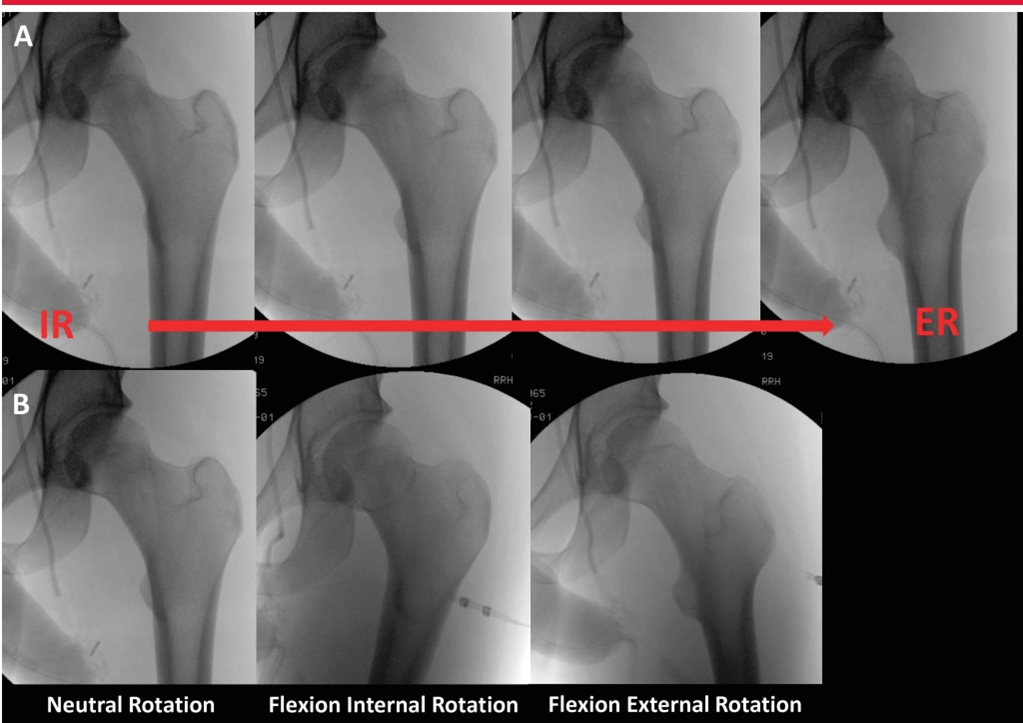

Интраоперационная рентгеноскопия обычно используется для оценки репозиции и фиксации перелома. Чтобы оценить рентгеноскопические изображения во время фиксации перелома, необходимо понимать взаимоотношения проксимальных отделов интактной бедренной кости и то, как они изменяются в зависимости от положения рентгеноскопического луча, положения ноги и нормальных анатомических изменений. Изображения проксимального отдела бедренной кости показывают стандартное соотношение между кончиком вертела и центром головки бедренной кости. Когда проксимальный отдел бедренной кости поворачивается наружу, угол оси шейки бедренной кости увеличивается, и шейка бедренной кости укорачивается (изображение ниже).

Рентгенограмма показывает рентгеноскопическое изображение того же бедра в прямой проекции от внутренней ротации (IR) до наружной ротации (ER). Обратите внимание на изменение контура бедра с IR на ER. Обратите внимание на внешний вид угла шеи и диафиза, когда он меняется от сгибания/IR к сгибанию/наружной ротации. Аналогично, сгибание и разгибание бедра может значительно изменить перспективу угла оси шейного отдела. В исследовании Bhashyam et al., сгибание, разгибание и ротация бедра оказывали синергетический эффект на измерение NSA.Когда сгибание и разгибание бедра находились в пределах 10° от нейтрального положения, ошибка измерения была минимальной. Поскольку пораженный тазобедренный сустав имеет тенденцию сгибаться и вращаться внутрь, это может создать иллюзию увеличения варусности.